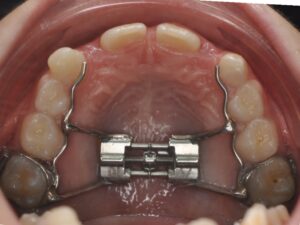

Il s’agit de l’orthodontie du jeune enfant. Elle permet d’intercepter un défaut de croissance ou d’éruption dentaire qui pourrait devenir irréversible s’il est pris en charge trop tard. De manière générale, il y a trois axes.

Il correspond à la réorientation des croissances des mâchoires supérieures et inférieures. En effet, tant que l’enfant est encore jeune, la croissance peut être déverrouillées, voire guidée afin qu’une croissance harmonieuse des mâchoires se fasse.

Il s’agit de la mastication, la respiration, la posture linguale, les habitudes déformantes. Elles font partie intégrante de la bonne posture des mâchoires et des dents. Elles seront également contrôlées et interceptées. Les appareils sont nombreux en fonction de la malocclusion, ils peuvent être fixes ou amovibles. Très souvent, l’interception pourra être associée à un rendez-vous chez : l'ORL, l'orthophoniste, le kinésithérapeute ou encore l'osthéopathe.